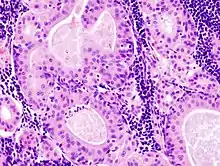

The appearance of this tumor under the microscope is unique. There are cystic spaces surrounded by two uniform rows of epithelial cells with centrally placed pyknotic nuclei. The cystic spaces have epithelium referred to as papillary infoldings that protrude into them. Additionally, the epithelium has lymphoid stroma with germinal center formation.